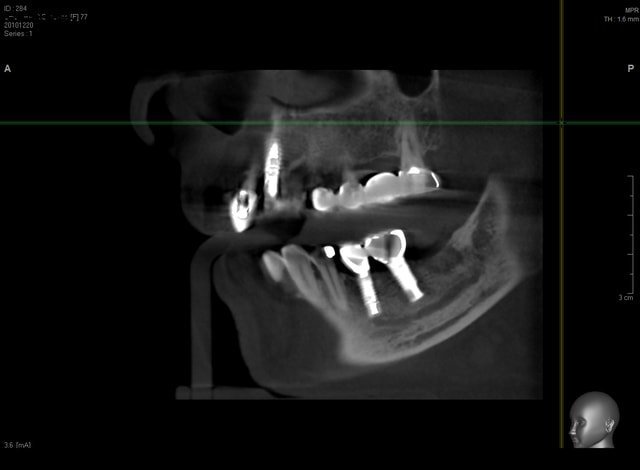

voilà des images de tout les jours....

Chevrier ecfaxb - Eugenol

Chevrier2 arpqfz - Eugenol

Guyot pr 2 pqmexp - Eugenol

Guyot pr 3 rztfoz - Eugenol

Scan greffe jzynvr - Eugenol

Scan greffe2 meswpp - Eugenol